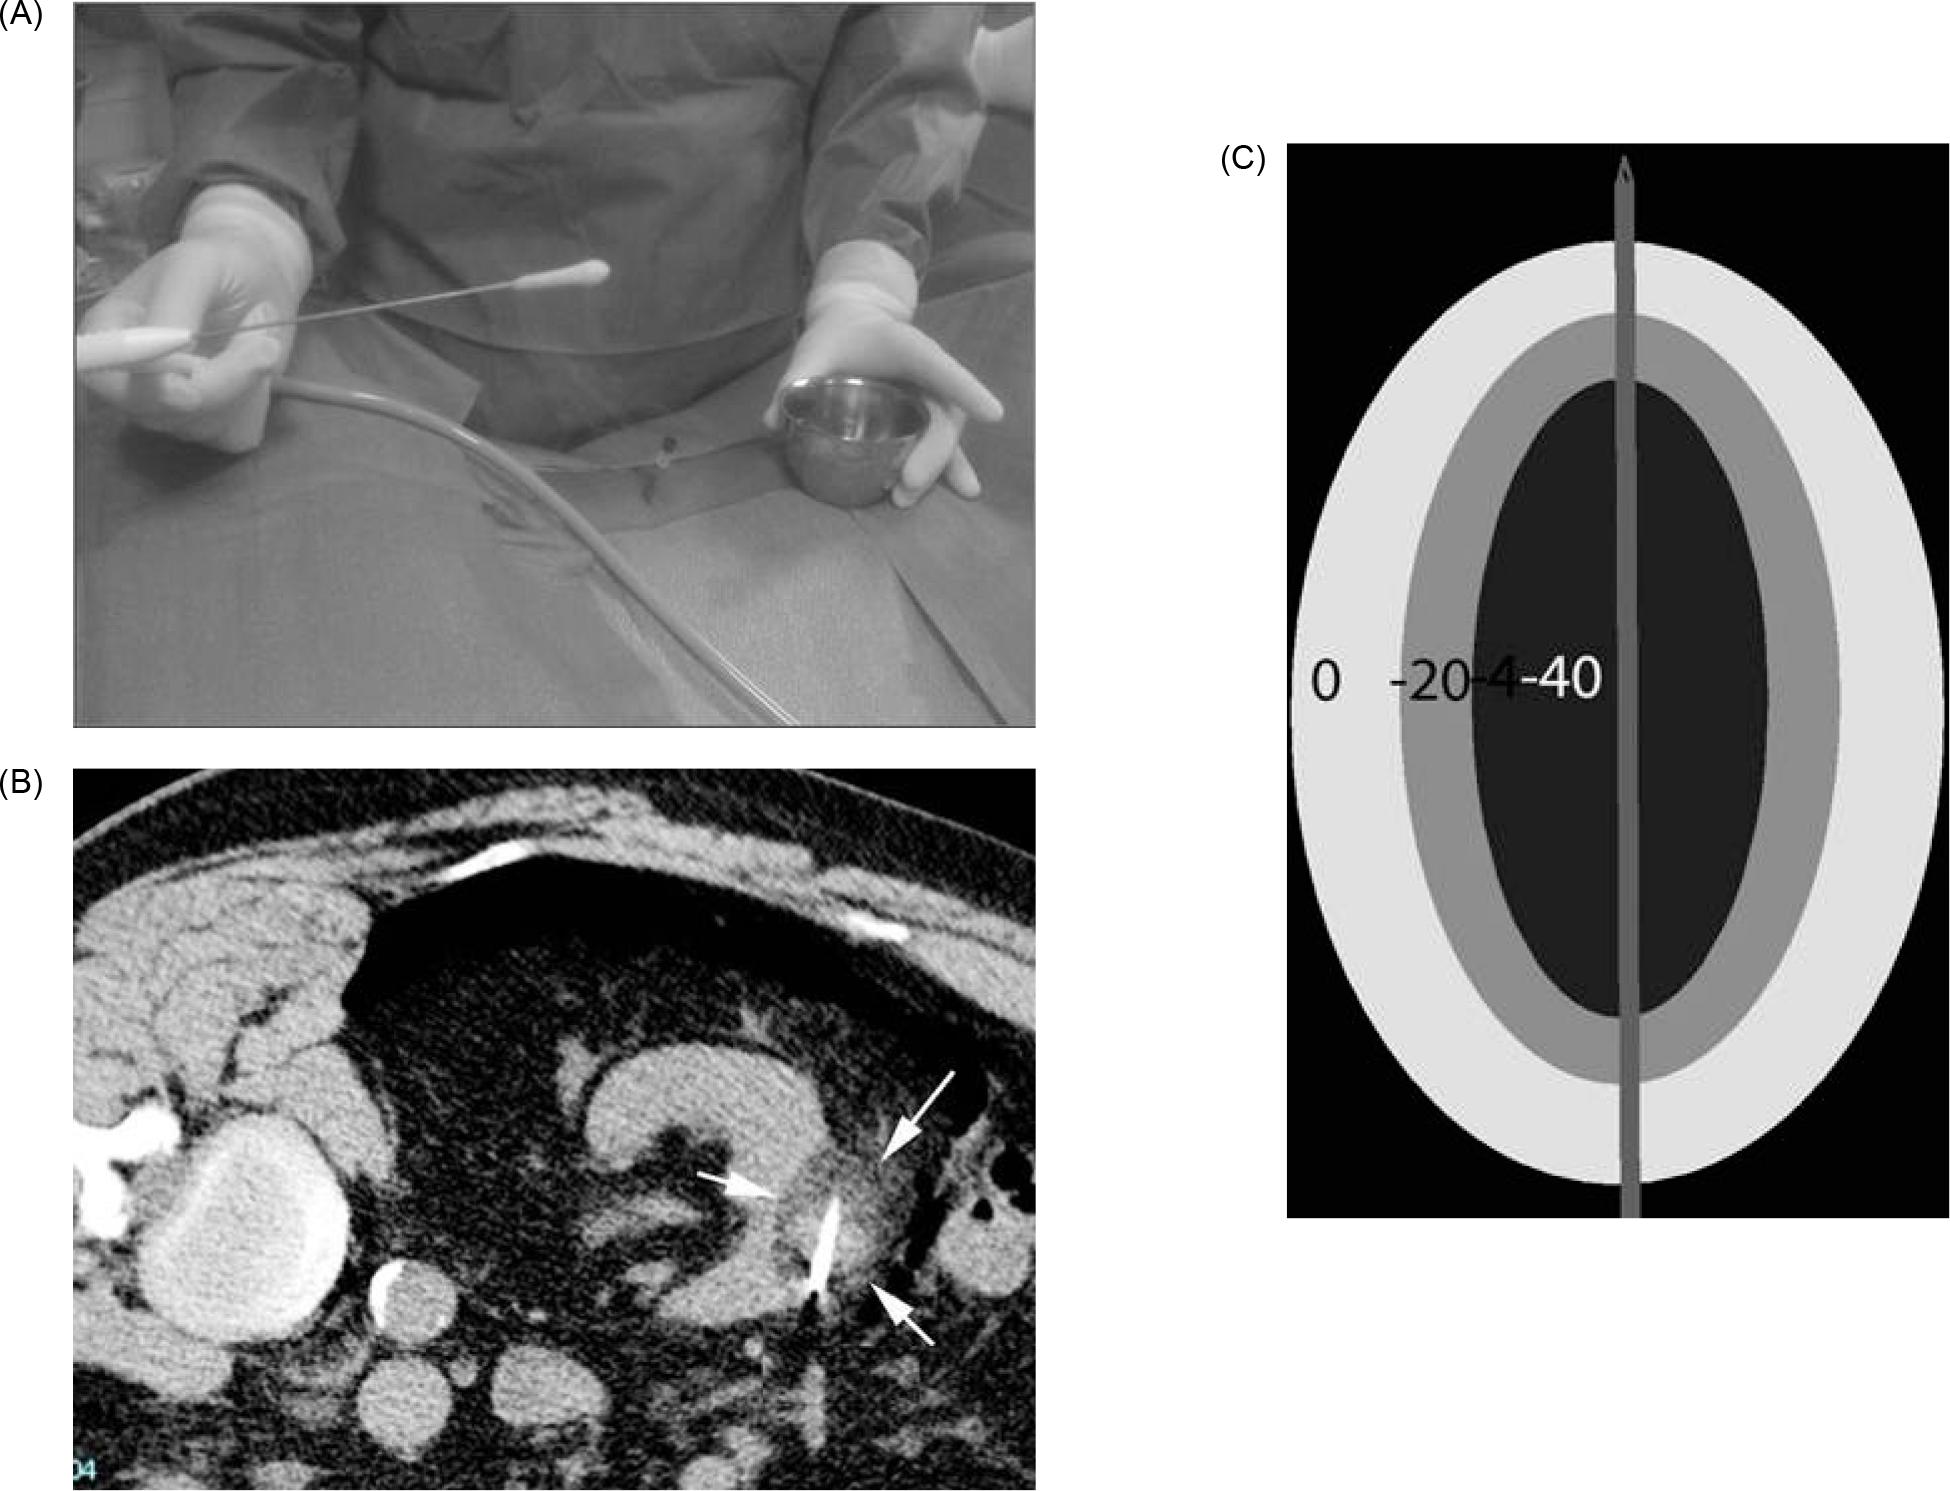

Microwave ablation is a form of electromagnetic radiation that typically oscillates between 900–2500 MHz (36). Like RFA, this fluctuation causes the continued realignment of polar molecules within tissue producing an increase in kinetic energy. This phenomenon, termed “dielectric hysteresis,” translates to rising temperature within the tissue, often above 100°C (15, 36). In MWA, these electromagnetic waves are delivered through one or more antennae inserted into the tissue (27). In contrast to RFA, MWA does not rely on tissue conductivity, and can effectively heat a variety of tissues regardless of electrical conductivity (37). This field effect provides for uniform heat generation (Figure 5). Thus, it is effective compared to RFA for lung, bone, and other tissues with high electrical impedance (37). Further, MWA has an increased ability to overcome the heat sink effect (38). This is an advantage for efficacy within highly vascular organs such as the kidneys, where increased blood flow can lead to the dispersion of thermal energy (27).

Figure 5: Depiction of microwave antenna generating a field of heat.